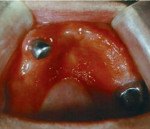

При осмотре полости рта выявляются явления гиперемии, отека, сухости слизистых оболочек, наличие петехиальных кровоизлияний, следы отпечатков зубов на слизистой щек и боковых поверхностях языка. При развитии аллергии к металлическим протезным материалам можно обнаружить нарушение целостности мостовидного протеза, особенно в месте пайки, наличие окисных пленок. Контактный аллергический стоматит, возникший после установки пластмассовых съемных зубных протезов, кроме вышеуказанных признаков характеризуется появлением на слизистой оболочке протезного ложа папилломатозных разрастаний.